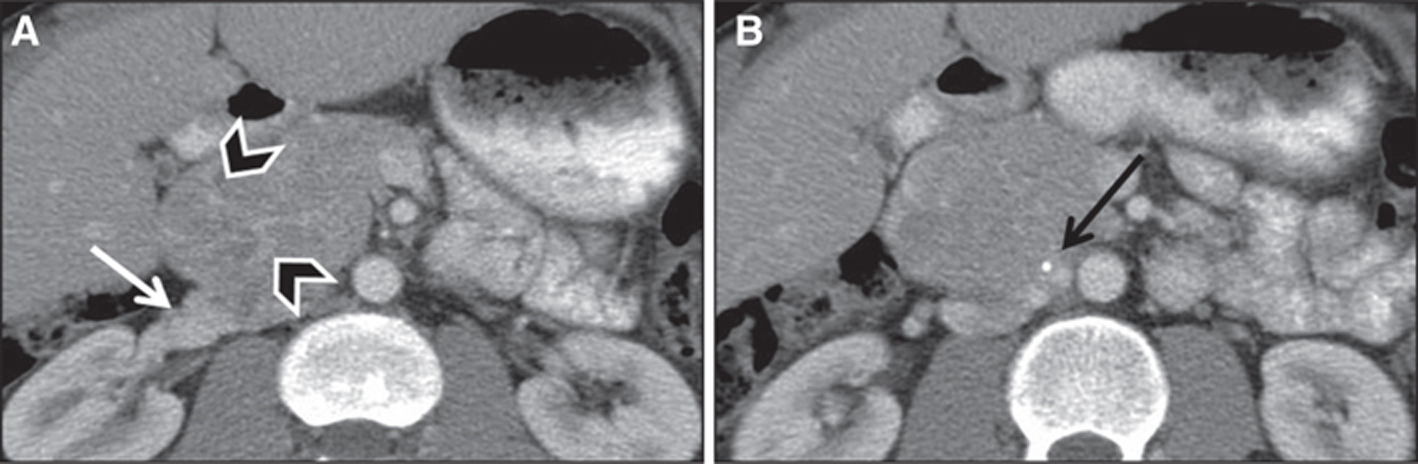

Fig 4

Figure 4 Paraganglioma in a 30-year-old male patient. Images obtained after administration of iodinated intravenous contrast demonstrate heterogeneously hyperenhancing retroperitoneal mass compressing the right renal vein (white arrow) with prominent vascular feeders (arrowheads) and a peripheral calcification (black arrow).